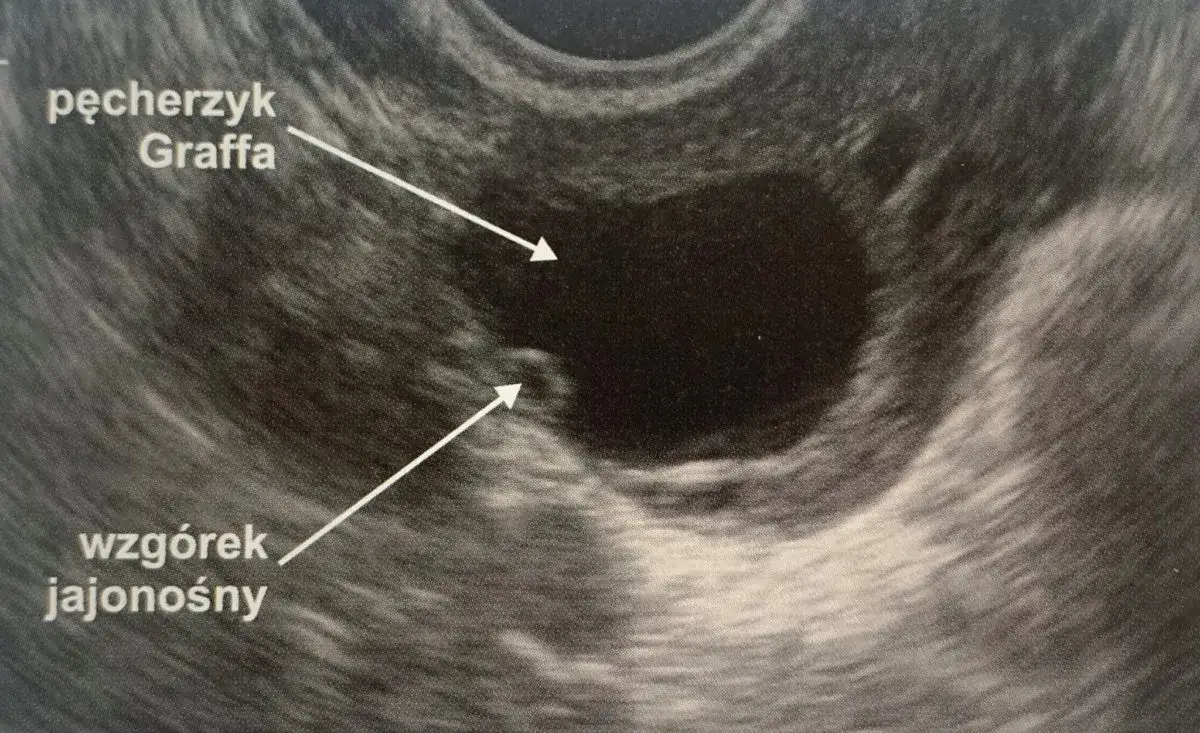

Warto pamiętać, że menopauza to naturalny proces starzenia się jajników, który polega na stopniowym wygaszaniu ich funkcji. Antykoncepcja hormonalna nie zatrzymuje tego procesu. Dostarcza ona zewnętrzne hormony, które regulują cykl i zapobiegają ciąży, ale nie wpływają na wewnętrzne zmiany zachodzące w jajnikach. Dlatego też, mimo przyjmowania tabletek, jest całkowicie możliwe, że Twój organizm wchodzi już w okres menopauzy, a Ty po prostu nie widzisz jej najbardziej oczywistych sygnałów.